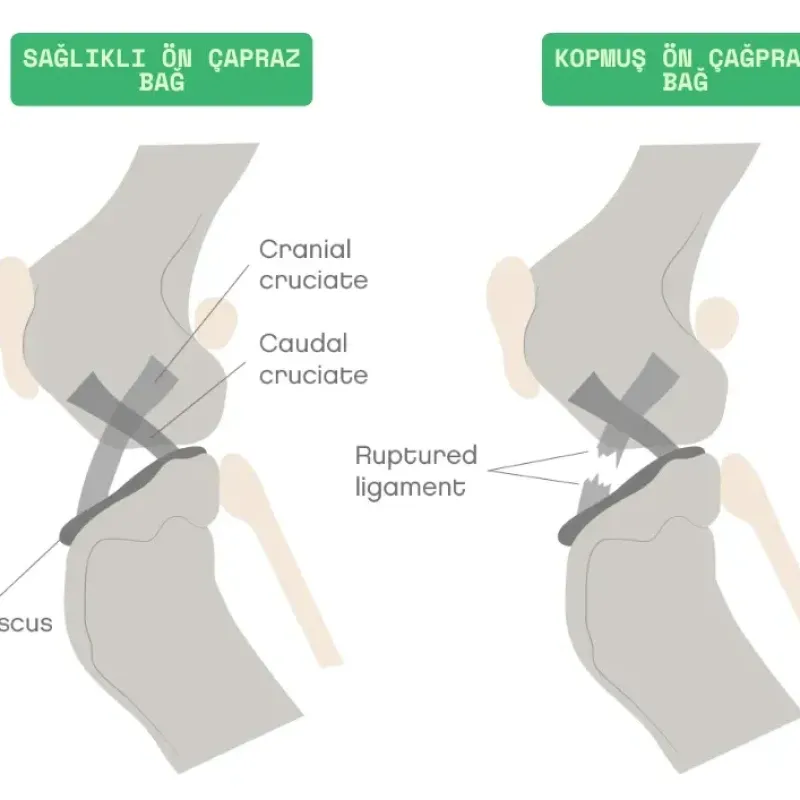

Köpeklerdeki kranial çapraz bağ (CrCL), insanlardaki ön çapraz bağ (ACL) ile aynıdır. Femur ile tibia arasında bağlantı kuran sert lifli, şerit şeklinde bir dokudur ve tibianın femur üstünden öne doğru kaymasını önler. Bu önleme diz ekleminin stabil halde çalışmasına katkı sağlar. Ayrıca diz ekleminin aşırı açılanmasını veya dönmesini önlemeye yardımcı olur.

İnsanlarda genellikle spor aktiviteleri esnasında ön çapraz bağ aniden kopar fakat köpeklerde bağ, aşırı travma nedeniyle aniden kopmak yerine, genellikle zamanla yavaşça dejenerasyona uğrar, tıpkı yıpranan bir ip gibi. Bu önemli fark, köpeklerde çapraz bağ yaralanması için önerilen tedavi seçeneklerinin, insanlar için önerilen tedavi seçeneklerinden bu kadar farklı olmasının başlıca nedenidir.

Bir diz ekleminde çapraz bağ yaralanmasını takiben hemen osteoartrit başlar ve bu kireçlenme ilerleyici nitelikte olduğu için şiddeti giderek artar. Aşınmanın ileri safhalarında CrCL normal mekanik işlevini kaybeder ve ağrılı aksama, mekanik aksama ile birlikte görülür. Bu noktada, mekanik aksamayı etkileyen faktörlerden biri, köpeklerde belirgin bir şekilde geriye doğru eğimli olan tibianın (kaval kemiği) üst kısmının şeklidir. Yetersiz CrCL'ye sahip köpeklerde bu eğimin sonucu, bacak her yüklenmede femurun eğiminden aşağı doğru kayar. Bazı köpeklerde, çapraz bağ yaralanması diz eklemi içerisindeki diğer yapılara ve özellikle menisküse zarar verebilir. Tibia yüzeyine dengesi.z bir bası oluşturan femur özellikle medial menisküslerde yırtıklara sebep olabilir.